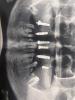

Заживление зубных имплантов: боль после процедуры у врача

Фото прикрепила в коментариях. Вот так прекрасно зажили мои импланты сегодня сказал врач. Прошло почти 4 месяца. Что то сегодня так больно что то делал то ли чистил то ли что. Один был зашит его открыл. Еще передний один железку убрал. Неделю дал что бы зажил тот который разрезал вот такие новости сказал день пожить на обезболивающих будет болеть и правда начало ныть😕